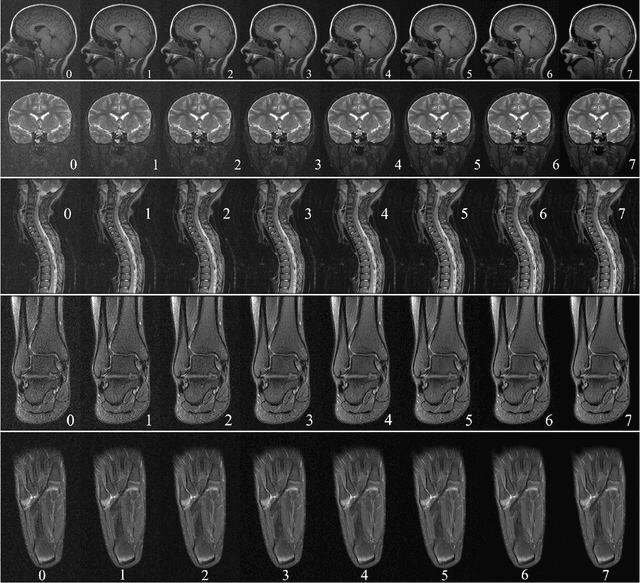

In clinical practice MR images are often first seen by radiologists long after the scan. If image quality is inadequate either patients have to return for an additional scan, or a suboptimal interpretation is rendered. An automatic image quality assessment (IQA) would enable real-time remediation. Existing IQA works for MRI give only a general quality score, agnostic to the cause of and solution to low-quality scans. Furthermore, radiologists' image quality requirements vary with the scan type and diagnostic task. Therefore, the same score may have different implications for different scans. We propose a framework with multi-task CNN model trained with calibrated labels and inferenced with image rulers. Labels calibrated by human inputs follow a well-defined and efficient labeling task. Image rulers address varying quality standards and provide a concrete way of interpreting raw scores from the CNN. The model supports assessments of two of the most common artifacts in MRI: noise and motion. It achieves accuracies of around 90%, 6% better than the best previous method examined, and 3% better than human experts on noise assessment. Our experiments show that label calibration, image rulers, and multi-task training improve the model's performance and generalizability.